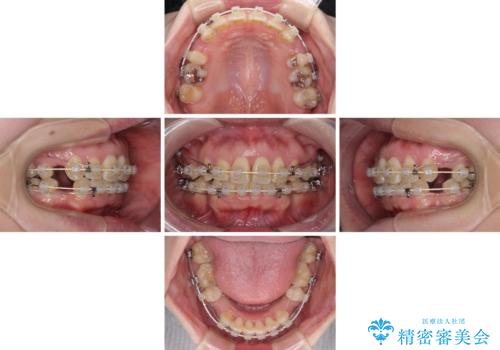

出っ歯による口の閉じにくさを治したい ワイヤー装置を用いた抜歯矯正

- 出っ歯と口の閉じにくさ、デコボコを気にして来院された患者様です。

口元の突出感を改善するため、上下左右第一小臼歯4本の抜歯を行い、ワイヤー装置による矯正治療を行うこととしました。

上下前歯の距離が大きかったため、上下の歯が接触するまでに時間がかかりました。

それでも目安である2年半で終えることができ、患者様には大変満足していただけました。